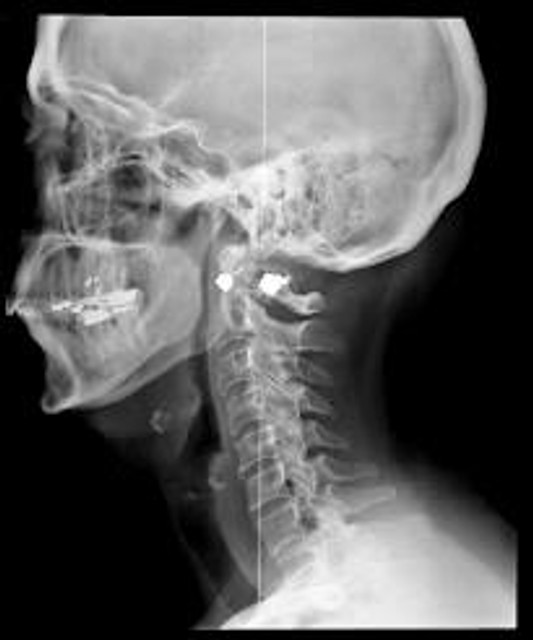

Astonishing new information about the damaging health effects of medical x-rays is the subject of a new book, Radiation from Medical Procedures, by John Gofman, M.D., Ph.D. Both a medical doctor and a nuclear physicist, Dr. Gofman is one of the world's leading experts in radiation damage. Dr. Gofman's evidence suggests that: Medical x-rays are responsible for an estimated 60 percent of all cancer deaths and 70 percent of all deaths from Ischemic Heart Disease (blockage of blood vessels).

For many years, studies have linked radiation exposure with most varieties of human cancers. Coming as a big surprise, Dr. Gofman's findings show that x-rays contribute to heart disease. What happens is this: x-rays cause mutations in the smooth muscle cells of the arteries, which makes the cells dystoreunctional and unable to process lipoproteins correctly. This in turn causes chronic inflammation of the arterial tissue, resulting in the accumulation of atherosclerotic plaque. This plaque eventually blocks the artery, resulting in heart attacks and strokes.

When one contemplates the implications of Dr. Gofman's conclusions, some alarming realities present themselves. First, medical radiation appears to be one of the principal causes of cancer and heart disease in America. Next, the amount of people who are affected is enormous. M.D.s order about 300 million xrays per year and dentists order another 100 million—perhaps helping to explain our increasing rates of cancer and other chronic diseases. Next, if one combines America's annual deaths from medical errors and prescription drugs (about 425,000) with the projected deaths from medical x-rays (about 750,000), this adds up to well over one million deaths per year being caused by our modern medical establishment. Thus, modern medicine would become the single largest cause of death in America.

Of course, diagnostic x-rays can be of benefit in certain situations, which is why they are still used—if overused. Dr. Gofman recommends that the total number of x-rays and the radiation dose of each be reduced. He believes that the number of x-rays could be cut by more than half without any loss of useful information. (Other researchers have estimated that up to 90 percent could be eliminated with no loss of useful data.) In addition, Dr. Gofman points out that x-rays are not the sole cause of cancer and heart disease. Rather, x-rays act as necessary co-factors in these diseases. That is, they are not the only factor involved in producing these diseases, but the disease will not happen without the x-ray.

If nothing else will get you to avoid x-rays, then consider this: X-rays bombard the atoms that make up your cells, "kicking" electrons out of their normal orbits and sending them flying at high speeds through your body's cells. These high-speed electrons crash into molecules that make up the genetic material in human cells and subject them to a uniquely violent kind of damage—mayhem that injures the genes so that they cannot be perfectly repaired (or even repaired at all). Put simply, exposure to x-rays can change the genetic coding of your cells, resulting in mutations that cause serious problems like cancer and heart disease. Do not expose yourself to x-rays unless absolutely necessary.